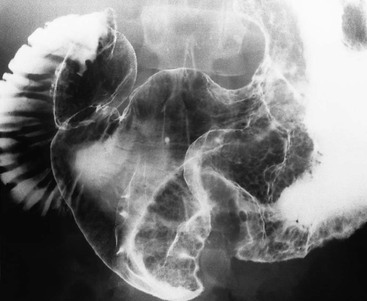

Crohn’s

Multiple aphthous (superficial) erosions are present on the antrum. Duodenal folds are thick and nodular (cobblestone mucosa).